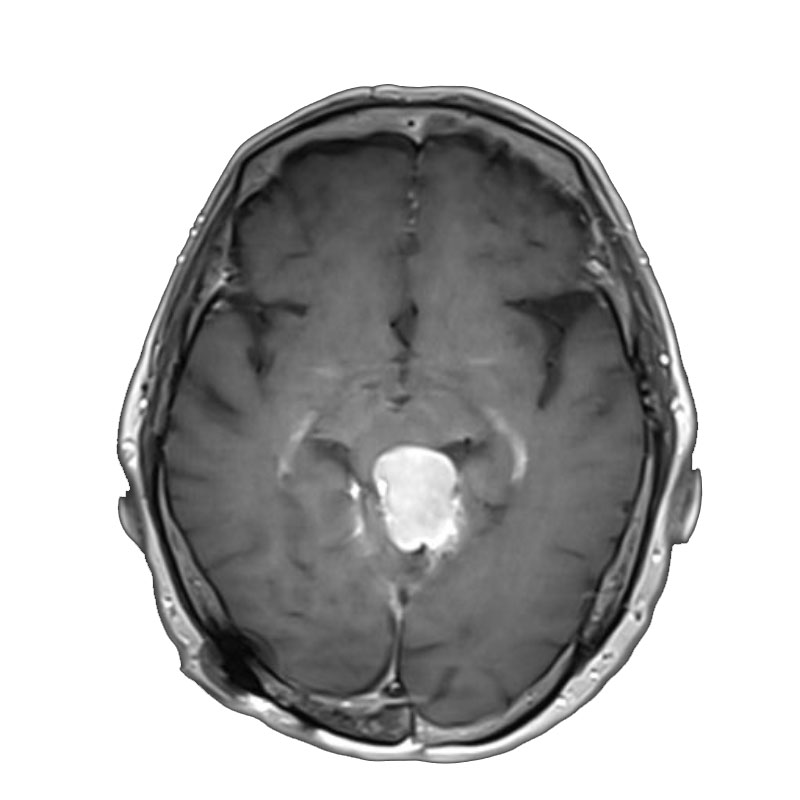

脳室内腫瘍

摘出術

北野/濵田